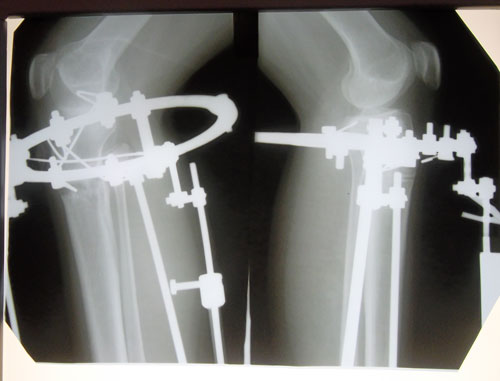

Здравствуйте, Tosha! По результатам рентгена, вы можете снять аппарат только с левой ноги у себя на месте в городе, там уже всё пересраслось. А правую, приедете на снятие аппарата 9 - 10 января(планируйте остаться на 4 дня в клинике) и привезёте аппарат.

Рентген

Вложения

SAM_7335.JPG

SAM_7336.JPG

Дата операции 25.07.2013г.

Дата снятия аппаратов 07.01.2014г.

Срок лечения 5 месяцев и 11 дней.

(большие сроки из за сильной деформации правой ноги)